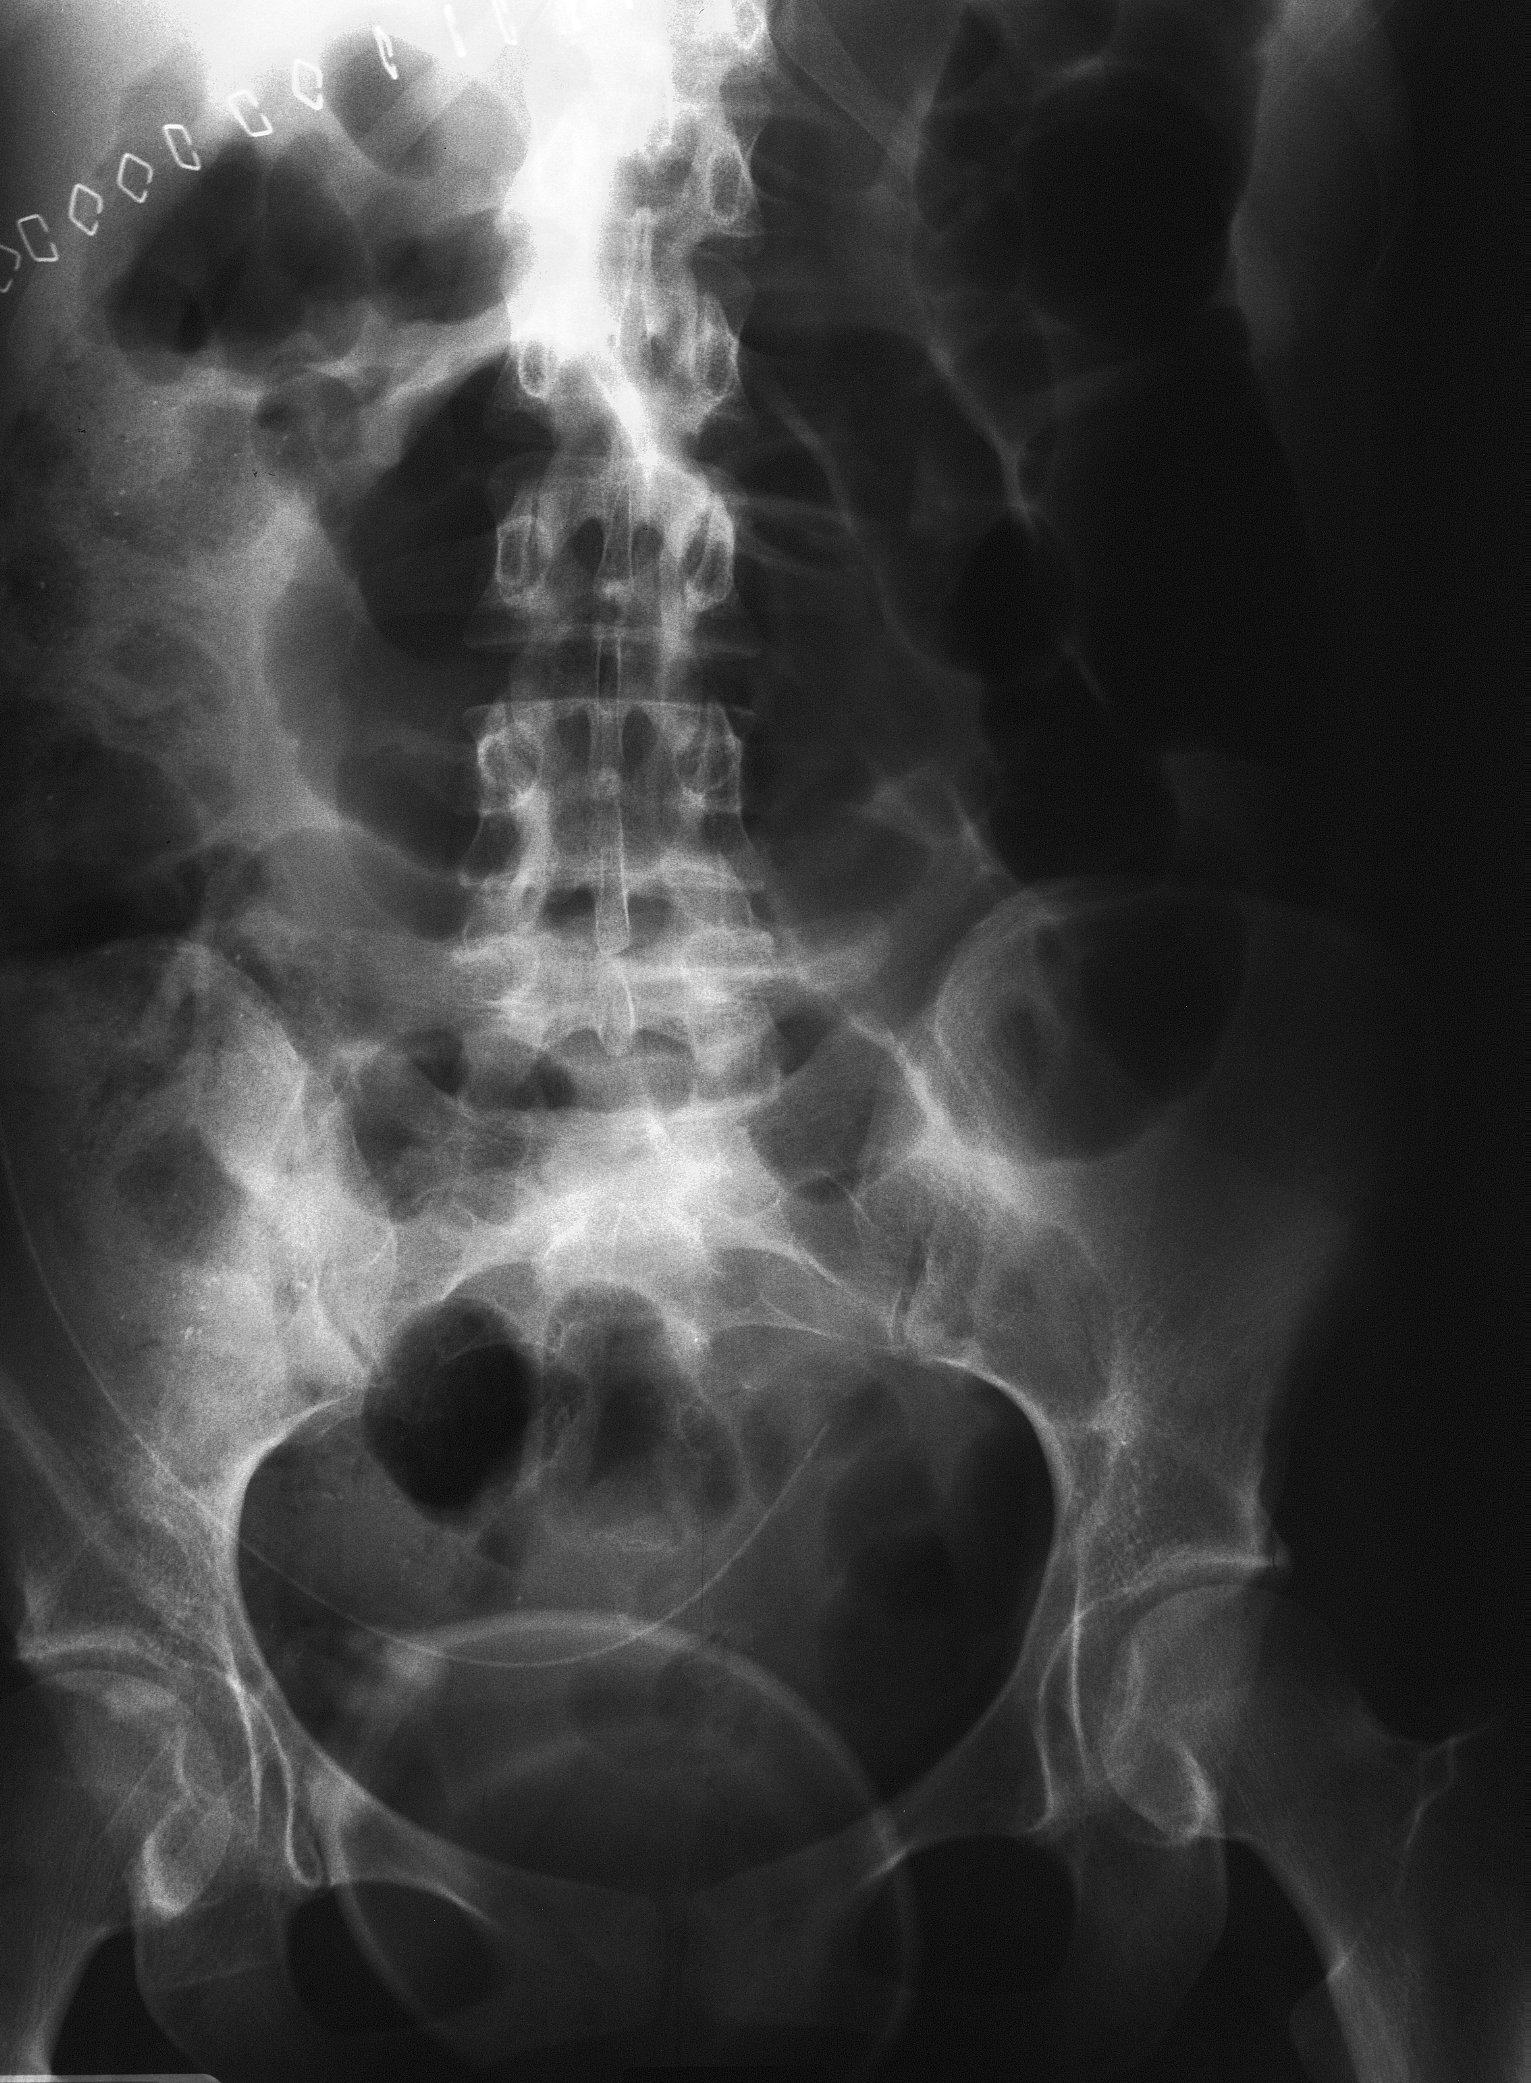

Chụp cắt lớp vi tính (CT Scan), X-quang bụng.